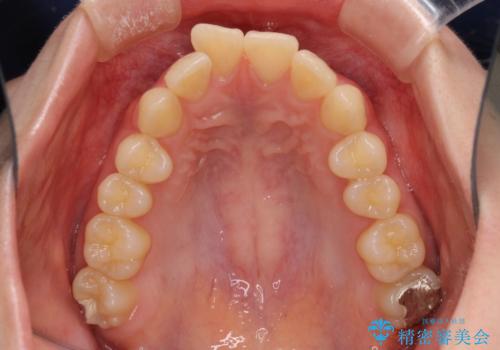

- 前歯2本が飛び出してることを気にして来院された患者様です。

全体的に黄ばんだ歯の色も気になるとのことで、マウスピース矯正により飛び出した前歯を治しつつ、ホームホワイトニングを併用して黄ばみを解消していくこととしました。

歯と歯の間を削ることで、飛び出した前歯が引っ込み、スッキリとした口元となりました。

歯の黄ばみも改善され、明るい歯並びとなりました。